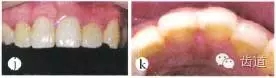

圖1j~k修復(fù)后4周口內(nèi)像